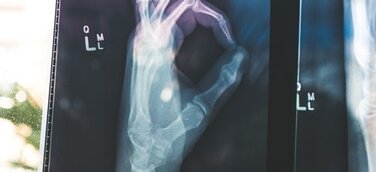

Medizinrecht – Arzthaftungsrecht – Behandlungsfehler:

Fehlbehandelter Bandscheibenvorfall im Segment LW 4/5, 27.000,- Euro, LG Flensburg, Az.: 3 O 28/15